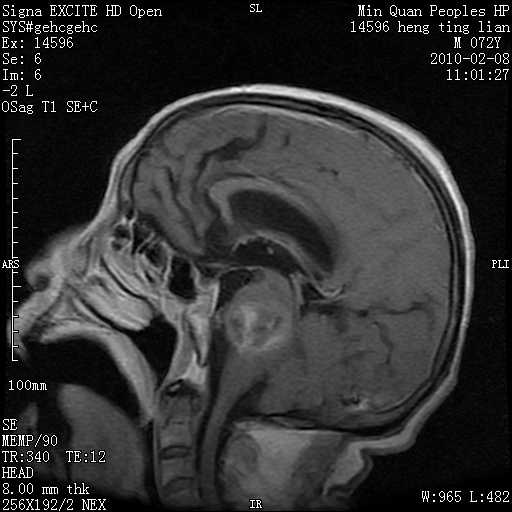

m,72,头疼,头晕两年,伴视力模糊三月,饮食呛咳两天。pe:颈部抵抗,左眼突出,左眼瞳孔约3mm,对光反射消失,双眼失明,伸舌困难,双肺呼吸音粗,心率110次/分,左上肢肌力i级,左下肢屈曲,肌张力高。现有08年2月19mri平扫及10年2月8日mri增强请会诊。ct病灶呈低密度伴散在点、片状等密度区,无明确钙化(无ct片资料可供上传)。[

脑外肿瘤,囊实性,环状不规则强化,内听道扩大,考虑神经源性肿瘤

左侧桥小脑区占位伴梗阻性脑积水----考虑 1神经鞘瘤 2室管膜瘤。

左侧桥小脑区神经鞘瘤伴梗阻性脑积水。

脑外肿瘤,病灶呈匍匐蔓延,表皮样囊肿可能性大。